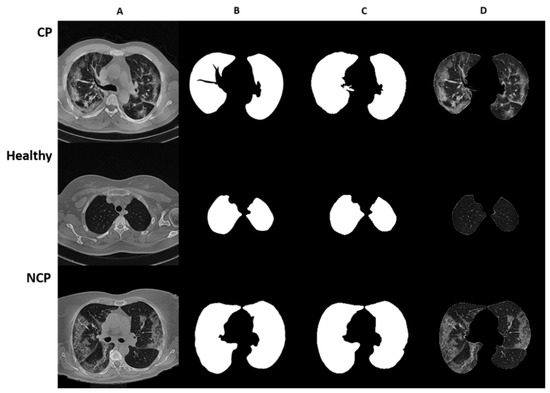

In this study, three subclasses, COVID Pneumonia (CP), Non-COVID Pneumonia (NCP), and healthy, were used. Out of 348 patients, 270 were assigned to the training set and 78 to the test set with these three subclasses. The distribution of the dataset is given in Table 1. For each of the three subclasses, CT slice images are represented in Figure 1 with original, manually segmented, AI-based segmented, and final merged format.

Figure 1. Representative images of lung CT segmentation. Rows depict CT slices of patients with COVID pneumonia, no pneumonia, and non-COVID pneumonia, respectively. (A) Original CT slice images; (B) manually segmented CT slice images; (C) AI-based segmentation of CT slice images; (D) merged image of the segmentation mask and original CT slice images.